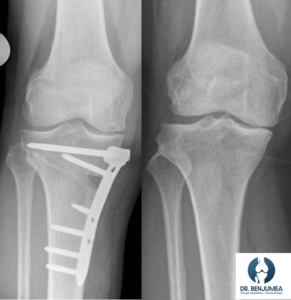

Osteotomías

A medio camino entre el tratamiento no quirúrgico y la prótesis de rodilla encontramos las osteotomías. Esta cirugía consiste en realizar un “corte” en el hueso, ya sea en la tibia o en el fémur y conseguir enderezar la pierna para trasladar el peso del cuerpo a otra zona de la rodilla. El objetivo es poder corregir desviaciones que estén provocando dolor, y en la rodilla con artrosis de una sola zona puede ser un tratamiento adecuado para los pacientes jóvenes con buenos resultados y logrando retrasar o evitar la colocación de una prótesis en el futuro.